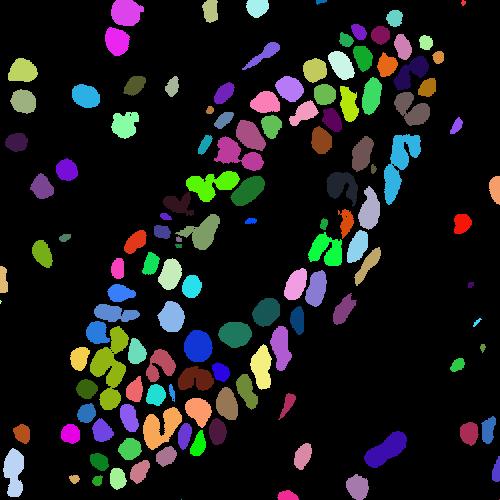

4.1.1 Voronoi labels

A Voronoi diagram is a partitioning of a plane into convex polygons (Voronoi cells) according to the distance to a set of points in the plane. There is exactly one point (seed point) in each cell and all points in a cell are closer to its seed point than other seed points. In our task, the detected points in an image can be treated as seed points to calculate the Voronoi diagram as shown in Fig. 1(b). For each Voronoi cell, assuming that the corresponding nucleus is located within the cell, then the Voronoi edges separate all nuclei well and the edge pixels belong to the background. This assumption holds for most of the nuclei because the detected points are around the centers and nuclear shapes are nearly convex (Fig. 3(b)).

Assigning the Voronoi edges as background pixels and the detected points (dilated with a disk kernel of radius 2) as nuclei pixels, we obtain the Voronoi point-edge label (Fig. 3). All other pixels are ignored during training. Note that although the pixels on the Voronoi edge between two touching nuclei may not necessarily be background, the edges are still helpful in guiding the network to separate the nuclei. The Voronoi labels aim to segment the central parts of nuclei and are not able to extract the full masks, because they lack the information of nuclear boundaries and shapes. To overcome this weakness, we generate another kind of labels that contain this complementary information.

(a) image

(b) true mask

(c) dist map

4.1.2 Cluster labels

Considering the color difference between nuclei and background pixels, it is feasible to perform a rough segmentation using clustering methods. We choose -means clustering to extract both nuclei and background pixels from the image, and generate the cluster labels. Given an image with pixels (), -means clustering aims to partition the pixels into clusters according to the feature vector of each pixel , such that the sum of within-cluster variances is minimized:

| (4) |

We use -means to divide all pixels into clusters: nuclei, background and ignored. The cluster that has maximum overlap with points label is considered as nuclei, and the cluster that has minimum overlap with the dilated points label is considered as background. The remaining one is the ignored class. The pixels of the ignored class are often located around the nuclear boundaries, which are hard for a clustering method to assign correct labels.

For the feature vector , color is a straightforward choice. However, clustering with color will result in wrong assignments for pixels inside some nuclei that have non-uniform colors. To cope with this issue, we add a distance feature. In a distance map (Fig. 3(c)), each value indicates the distance of that pixel to the closest nuclear point and therefore incorporates the spatial information. In particular, the pixels that belong to nuclei should be close enough to points in the label while background pixels are relatively far from those points. The distance map can be calculated by the distance transform of the complement image of detected points. Combining the distance value with the RGB color values as the feature vector in -means clustering, we obtain the initial cluster labels. is the clipped value by truncating large values to 20 and , , are normalized values such that every feature has similar value range.

The cluster label (Fig. 1(b)) is generated by refining the clustering result with morphological dilation and erosion, which are done separately in each Voronoi cell to avoid connecting close nuclei. The cluster labels have more shape information about the nuclei compared with the Voronoi labels, at the expense of more errors and uncertainties. We argue that these two types of labels are complementary to each other and will jointly lead to better results.